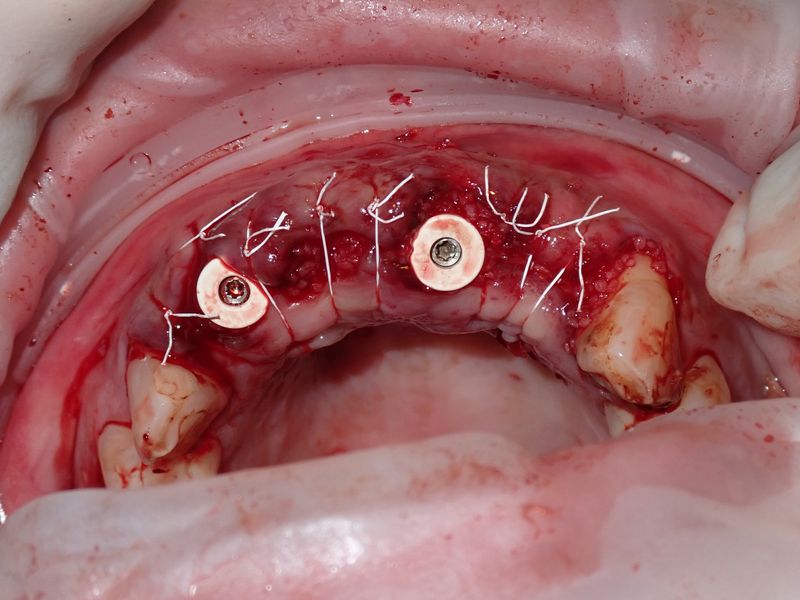

fredlibc | all galleries >> Galleries >> MTiu - immediate 12 and 21 > PA280029.JPG

PA280029.JPG